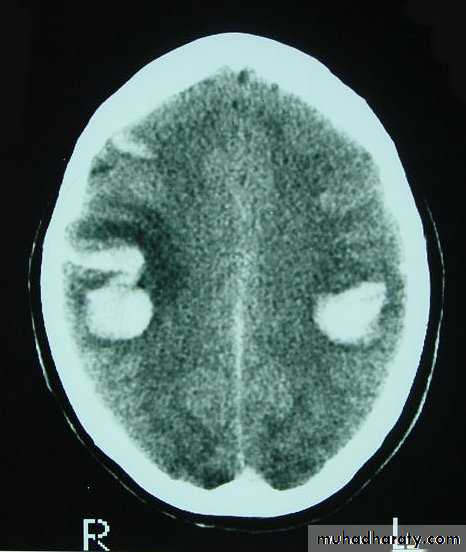

Chronic Subdural Haematoma

Most common in infants and in adults over 60 years of age secondary to SLIGHT blow to the head which may pass unnoticed.

Source of bleeding (haematoma): usually from bridging veins as they pass to the venous sinuses.

The patients present with progressive neurological deficits more than 3 weeks after the trauma.

The initial head injury is often completely forgotten.

CT scan: the acute clotted blood is initially appears white (hyperdence), but as it liquefies, it slowly becomes black (hypodense).

They should be drained if they continue to enlarge.

They are evacuated by drilling burrholes over the collection and washing it out with warmed saline.